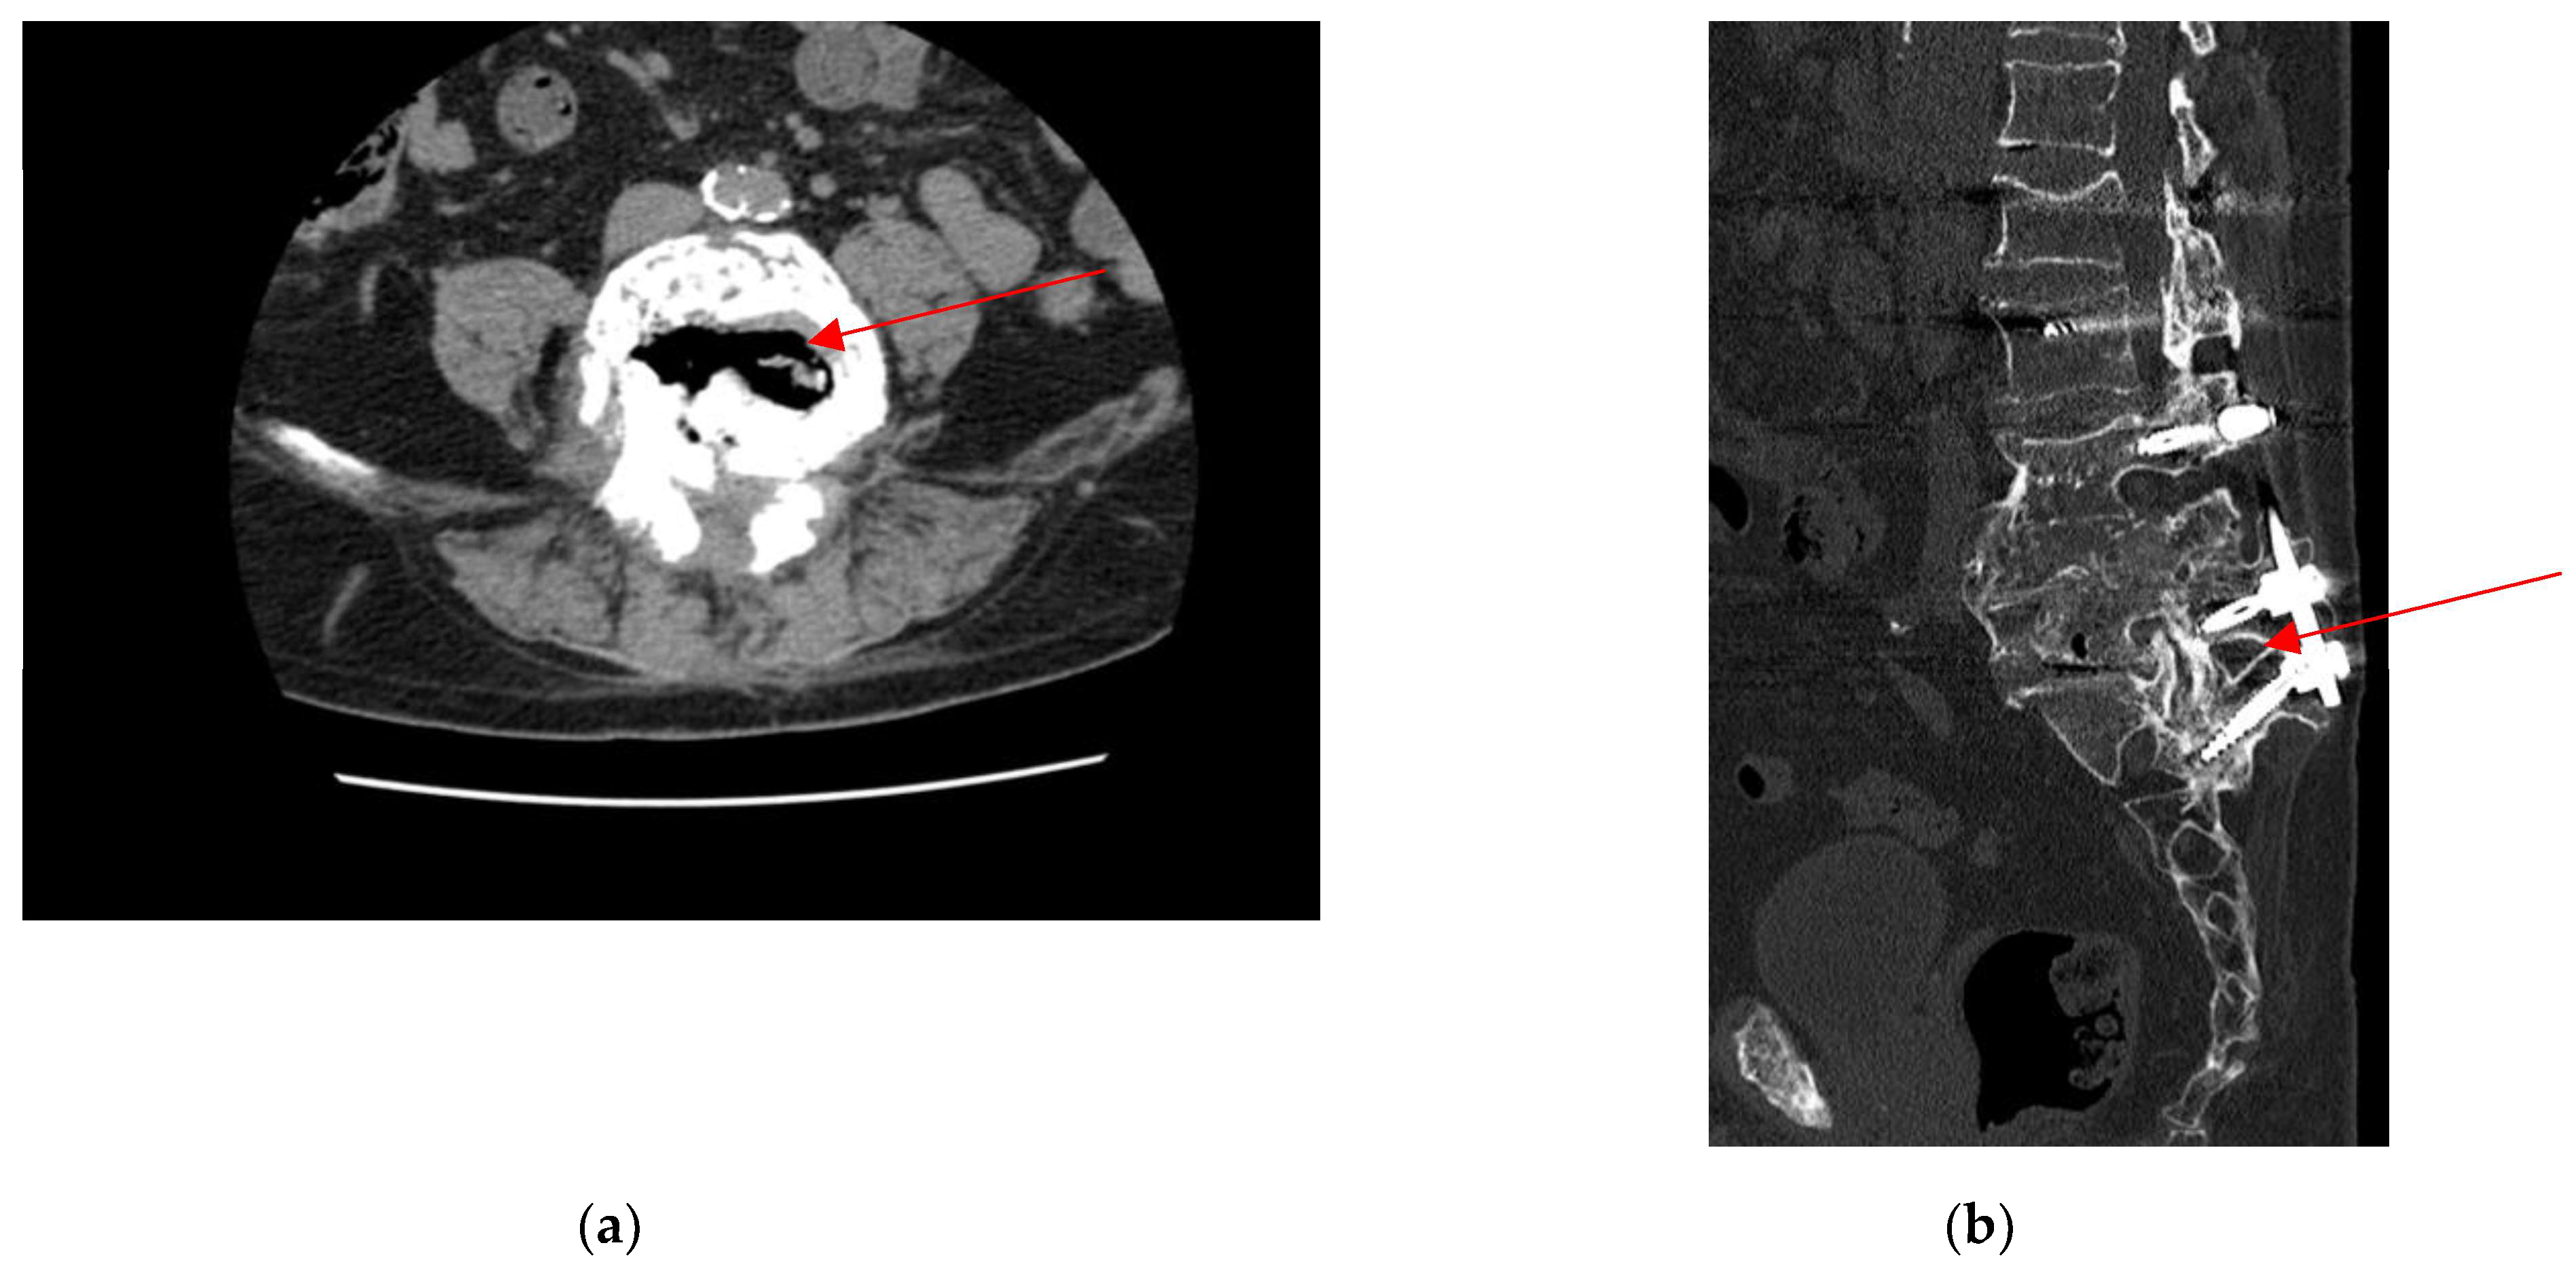

2.3. Admission to Infectious Diseases Unit

2.4. Neurosurgery Evaluation